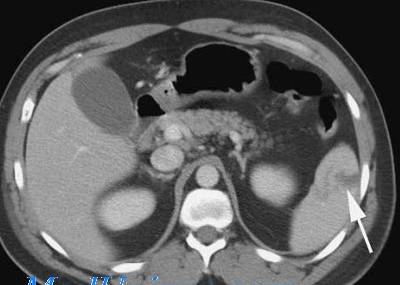

Компьютерна томография — это способ диагностики, позволяющий увидеть картину развития заболевания. Исследование проводят на органах, расположенных в брюшной полости.

С помощью такого метода выявляют изменения в состоянии узлов.